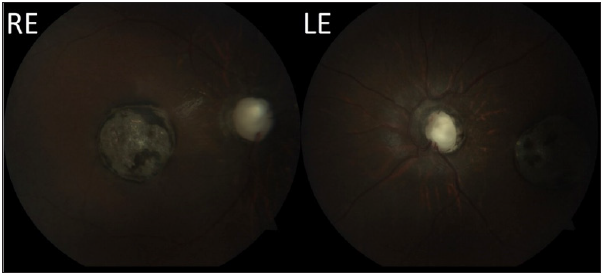

Siblings aged Nine (female) and Five (Male), were referred to the ophthalmology OPD with diminution of vision observed since few months of constant degree. Both children were born to a non-consanguineous marriage and had normal birth and developmental history. Both were known case of Type 1 Diabetics under treatment. On ophthalmologic examination, the elder female child had accommodative esotropia of about 45 degrees. Best Corrected Visual Acuity (BCVA) was counting fingers at 1 meter in both the eyes. The patient also had microphthalmos and microcornea. On retinoscopy, she had a refractive error of -13 dioptre of myopia along with 1.75 dioptre of myopic astigmatism at 45 degrees. The fundus of both eyes showed a pale disc with a large deep cup which was broader inferiorly suggestive of optic disc coloboma. A large single circular scar of about three-disc diameter in size at the macula which was hypopigmented and had small patches of hyperpigmentation in it suggestive of an old posterior uveitis secondary to toxoplasmosis (Figure 1). Also, the patient had coloboma of the choroid inferiorly. Intraocular Pressure was normal in both eyes. The younger male sibling had accommodative esotropia of about 70 degrees. Best Corrected Visual Acuity (BCVA) was only hand movements. The patient also had microphthalmos and microcornea. On retinoscopy, he had a refractive error of -5 dioptres of myopia in the right eye while the left eye was near emmetropia. Patient also had horizontal nystagmus. The Fundus of both eyes showed a pale disc with peripapillary hyperpigmentation, radially arranged vessels, disc excavation with abnormal tissue in its centre-suggestive of morning glory syndrome (Figure 2). Furthermore, the patient had small, half disc diameter hypopigmented patch in both eyes at the macula presumed to be a milder version of the same condition of the elder sister. The patient also had coloboma of the choroid inferiorly. Intraocular Pressure was normal in both eyes. Both patients had no diabetic retinopathy changes and were found to be normal systemically. Both patients had normal mental growth. The parents had normal anterior and posterior segment findings and no similar history was present in the family. Both the children were referred to higher institution for Low Vision Aids (LVA) and on follow-up were found to be doing fine in special school.

Figure 1:Fundus photographs of Right Eye (RE) and Left Eye (LE) of the elder sibling.